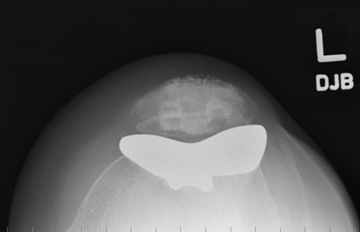

Under an anaesthetic, a large incision is made in the front of the knee and the knee joint is exposed. The groove in the femur (trochlea groove) is reshaped and a metal replacement is cemented in place. The undersurface of the patella is then cut flat and a plastic button is cemented onto it. The plastic button can then glide up and down in the metal groove.